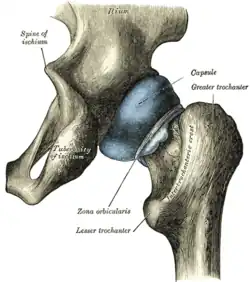

Gelenkkapsel, -flüssigkeit und -raum

Umhüllt wird das Hüftgelenk von der kräftigsten Gelenkkapsel des menschlichen Körpers, der straffen Hüftgelenkskapsel (Capsula articularis coxae). Sie wird über innerhalb der Kapsel gelegene Bänder stabilisiert und in der Mitte vom Ringband umgurtet. Bei Pferden und Raubtieren gibt es mit dem Musculus articularis coxae einen kleinen Skelettmuskel, der die Gelenkkapsel strafft.[2]

Äußere Schicht

Die äußere Schicht der Gelenkkapsel (Membrana fibrosa capsulae) entspringt am Limbus acetabuli und überdeckt trichterförmig fast vollständig den Oberschenkelknochenhals, um vorne an der Linie zwischen den beiden Oberschenkelrollhügeln (Linea intertrochanterica) zu inserieren. Hinten (dorsal) ist die Ansatzlinie etwa fingerbreit oberhalb des Randes (Crista intertrochanterica) zwischen den Oberschenkelknorren (Trochanter major und Trochanter minor) entfernt.

Bänder außerhalb der Kapsel

- Das Ringband (Zona orbicularis) liegt wie ein Kragen um die engste Stelle des Oberschenkelknochenhalses (Collum femoris). An der Innenfläche der Gelenkkapsel ist es als deutlicher Ringwulst zu erkennen, während es außen durch die anderen Bänder, die teilweise in sie einstrahlen, verdeckt ist.